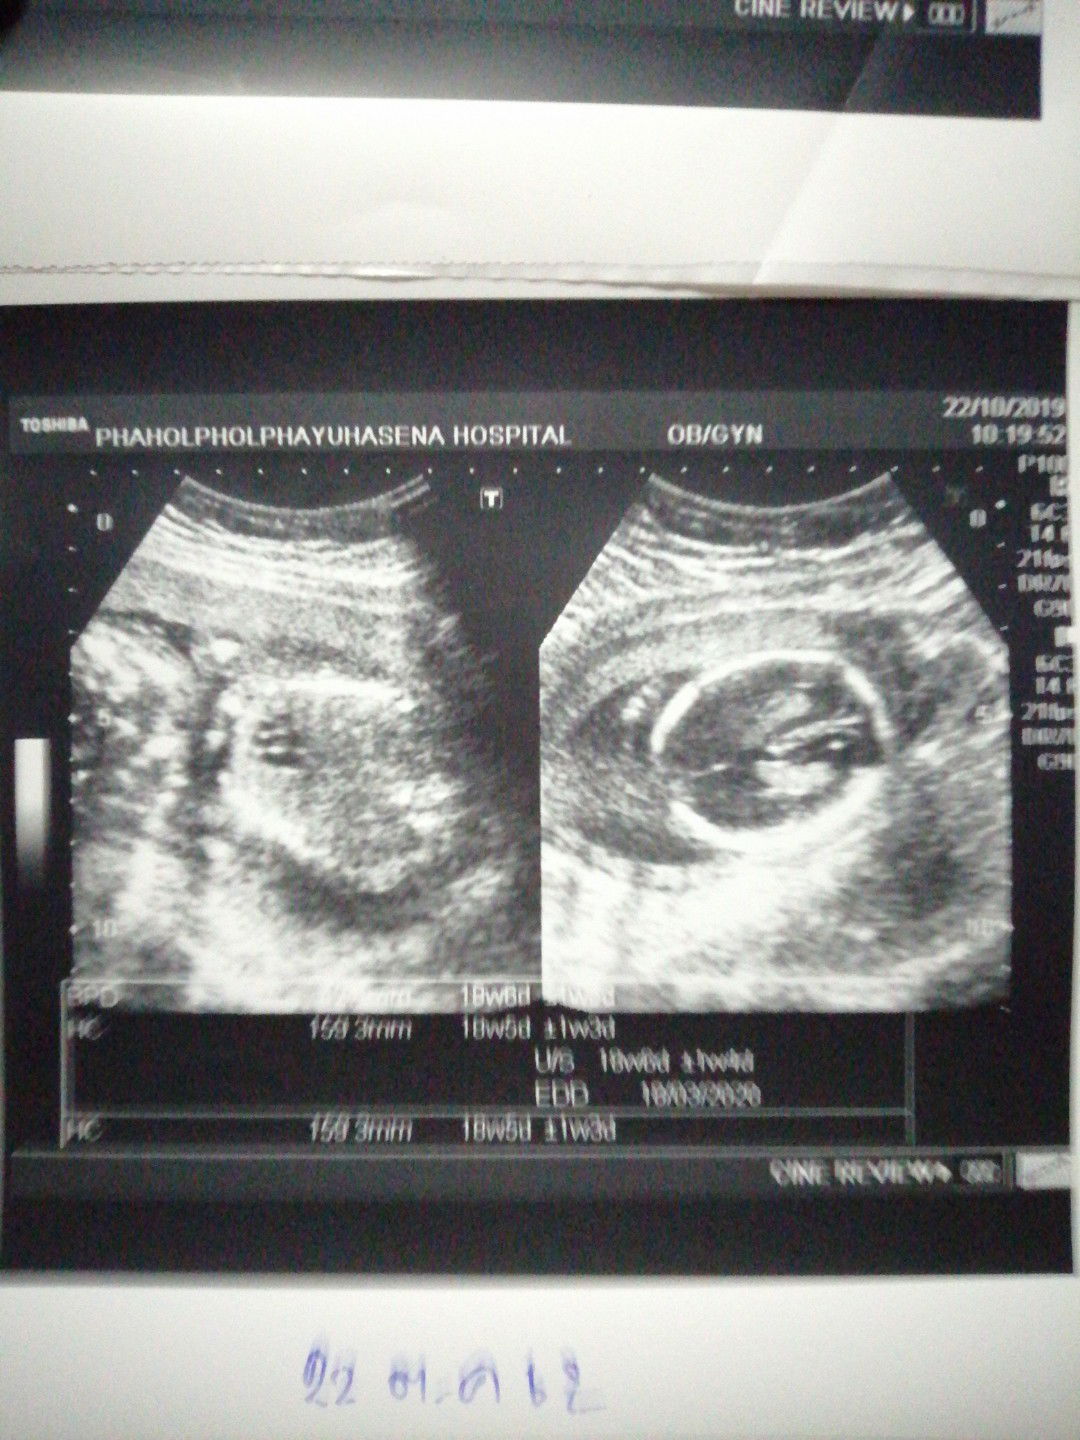

สอบถาม​เรื่อง​รูป​อัลต้าซาวด์หน่อยค่ะ

อยากให้แม่ๆช่วยวิเคราะห์​ว่ารูปอัลต้าซาวด์ดูยังไงคะ​ ใครรู้ช่วยบอกให้รู้ทีค่ะ​ มองรูปไม่เป็นค่ะ​ ซาวด์ครั้งแรกค่ะ​ หมอรีบไม่ได้บอกอะไรมากค่ะบอกแค่ว่าเด็กปกติดี​ ขอบคุณ​ล่วงหน้าค่ะ?

เป็นรูปส่วนหัว กับตัวน้องค่ะ